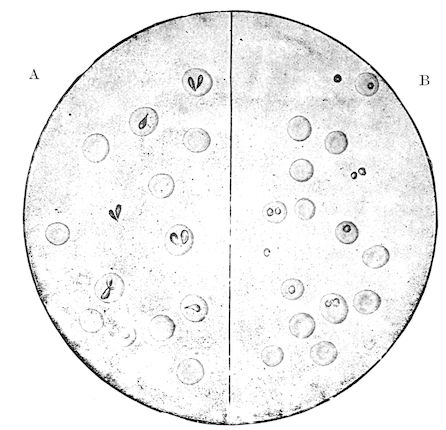

| Cœnurosis (Gid, sturdy, turn-sick) | 467 | |||

| Peritoneal cysticercosis | 485 | |||

| II. | HERNIÆ | 487 | ||

| Congenital herniæ | 487 | |||

| Perineal hernia of young pigs | 487 | |||

| Umbilical hernia | 488 | |||

| Acquired herniæ | 489 | |||

| Hernia of the rumen | 490 | |||

| Hernia of the abomasum | 493 | |||

| Hernia of the intestine | 494 | |||

| Treatment of herniæ | 495 | |||

| Diaphragmatic hernia | 496 | |||

| Eventration | 499 | |||

| Fistulæ of the digestive apparatus | 500 | |||

| SECTION VII. | ||||

| GENITO-URINARY REGIONS. | ||||

| Diseases of the Urinary Apparatus | 502 | |||

| I. | POLYPI OF THE GLANS PENIS AND SHEATH | 506 | ||

| Inflammation of the sheath | 506 | |||

| Persistence of the urachus | 508 | |||

| xiv | ||||

| II. | DISEASES OF THE BLADDER | 511 | ||

| Acute cystitis | 511 | |||

| Chronic cystitis | 513 | |||

| Urinary lithiasis. Calculus formation | 514 | |||

| Calculi in bovine animals | 515 | |||

| Urinary calculi in sheep | 518 | |||

| Paralysis of the bladder | 519 | |||

| Eversion of the bladder | 519 | |||

| Hæmaturia | 520 | |||

| III. | DISEASES OF THE KIDNEYS | 527 | ||

| Congestion of the kidneys | 527 | |||

| Acute nephritis | 528 | |||

| Chronic nephritis | 530 | |||

| Hydro-nephrosis | 531 | |||

| Infectious pyelo-nephritis | 533 | |||

| Suppurative nephritis and perinephritis | 537 | |||

| The kidney worm (Sclerostoma pinguicola) of swine | 539 | |||

| IV. | GENITAL APPARATUS | 542 | ||

| Vaginitis | 543 | |||

| Acute vaginitis | 544 | |||

| Contagious vaginitis | 545 | |||

| Croupal vaginitis | 545 | |||

| Chronic vaginitis | 546 | |||

| Metritis | 547 | |||

| Septic metritis | 547 | |||

| Acute metritis | 550 | |||

| Chronic metritis | 552 | |||

| Epizootic abortion in cows | 553 | |||

| Salpingitis—Salpingo-ovaritis | 555 | |||

| Torsion of the uterus | 556 | |||

| Tumours of the uterus | 559 | |||

| Tumours of the ovary | 559 | |||

| Genital malformations | 560 | |||

| Imperforate vagina | 560 | |||

| Nympho-mania | 562 | |||

| V. | DISEASES OF THE MAMMARY GLANDS | 565 | ||

| Physiological anomalies | 567 | |||

| Wounds or traumatic lesions | 568 | |||

| Chaps and cracks | 568 | |||

| Milk fistulæ | 569 | |||

| Inflammatory diseases | 570 | |||

| Congestion of the udder | 570 | |||

| Mammitis | 571 | |||

| Acute mammitis | 573 | |||

| Contagious mammitis in milch cows | 580 | |||

| Chronic mammitis | 581 | |||

| Gangrenous mammitis of milch ewes | 583 | |||

| Gangrenous mammitis in goats | 584 | |||

| xv | Cysts of the udder | 585 | ||

| Tumours of the udder | 585 | |||

| Verrucous papillomata of the udder | 586 | |||

| VI. | DISTURBANCE IN THE MILK SECRETION AND CHANGES IN THE MILK | 587 | ||

| Microbic changes in milk. Lactic ferments | 588 | |||

| VII. | MALE GENITAL ORGANS | 594 | ||

| Tumours of the testicle | 594 | |||

| Accessory glands of the genital apparatus | 597 | |||

| SECTION VIII. | ||||

| DISEASES OF THE SKIN AND SUBCUTANEOUS CONNECTIVE TISSUE. | ||||

| I. | ECZEMA | 599 | ||

| Acute eczema | 599 | |||

| Chronic eczema | 600 | |||

| Sebaceous or seborrhœic eczema | 601 | |||

| Eczema due to feeding with potato pulp | 603 | |||

| Impetigo in the pig | 605 | |||

| Acne in sheep | 606 | |||

| Fagopyrism (Buckwheat poisoning) | 606 | |||

| II. | PHTHIRIASIS | 608 | ||

| Scabies—Scab—Mange | 611 | |||

| Scabies in sheep | 611 | |||

| Sarcoptic scabies | 612 | |||

| Psoroptic mange—Sheep scab | 614 | |||

| The tobacco-and-sulphur dip | 626 | |||

| Lime-and-sulphur dips | 627 | |||

| Arsenical dips | 632 | |||

| Carbolic dips | 633 | |||

| Chorioptic mange—Symbiotic mange—Foot scab | 636 | |||

| Mange in the ox | 638 | |||

| Sarcoptic mange | 638 | |||

| Psoroptic mange | 639 | |||

| Chorioptic mange | 640 | |||

| Mange in the goat | 641 | |||

| Sarcoptic mange | 641 | |||

| Chorioptic mange | 642 | |||

| Mange in the pig | 642 | |||

| Demodecic mange | 643 | |||

| Demodecic mange in the ox | 644 | |||

| Demodecic mange in the goat | 644 | |||

| Demodecic mange in the pig | 644 | |||

| Non-psoroptic forms of acariasis | 645 | |||

| Hypodermosis in the ox (warbles) | 646 | |||

| xvi | ||||

| III. | RINGWORM | 649 | ||

| Ringworm in the sheep, goat, and pig | 653 | |||

| IV. | WARTS IN OXEN | 655 | ||

| Urticaria in the pig | 656 | |||

| Scleroderma | 657 | |||

| V. | SUBCUTANEOUS EMPHYSEMA | 659 | ||

| SECTION IX. | ||||

| DISEASES OF THE EYES. | ||||

| Foreign bodies | 661 | |||

| Conjunctivitis and keratitis | 662 | |||

| Verminous conjunctivitis | 662 | |||

| Verminous ophthalmia of the ox | 663 | |||

| SECTION X. | ||||

| INFECTIOUS DISEASES. | ||||

| Cow-pox—Vaccinia | 665 | |||

| Cow-pox and human variola—Preparation of vaccine | 669 | |||

| Tetanus | 670 | |||

| Actinomycosis | 672 | |||

| Actinomycosis of the maxilla | 673 | |||

| Actinomycosis of the tongue | 674 | |||

| Actinomycosis of the pharynx, parotid glands and neck | 675 | |||

| Tuberculosis | 682 | |||

| Tuberculosis of the respiratory apparatus | 690 | |||

| Tuberculosis of the serous membranes | 694 | |||

| Tuberculosis of lymphatic glands | 696 | |||

| Tuberculosis of the digestive tract | 699 | |||

| Tuberculosis of the genital organs | 700 | |||

| Tuberculosis of bones and articulations | 701 | |||

| Tuberculosis of the brain | 702 | |||

| Tuberculosis of the skin | 703 | |||

| Acute tuberculosis—Tuberculous septicæmia | 704 | |||

| Swine fever—Verrucous endocarditis and pneumonia of the pig | 710 | |||

| Swine fever | 710 | |||

| Verrucous endocarditis of the pig | 713 | |||

| Pneumonia of the pig | 714 | |||

| Hæmorrhagic septicæmia in cattle | 716 | |||

| SECTION XI. | ||||

| OPERATIONS. | ||||

| I. | CONTROL OF ANIMALS | 720 | ||

| Control of oxen | 720 | |||

| Partial control | 720 | |||

| Control of the limbs | 720 | |||

| xvii | General control | 722 | ||

| Control by casting | 723 | |||

| Control of sheep and goats | 725 | |||

| Control of pigs | 725 | |||

| Anæsthesia | 726 | |||

| II. | CIRCULATORY APPARATUS | 727 | ||

| Bleeding | 727 | |||

| Bleeding in sheep | 727 | |||

| Bleeding in the pig | 728 | |||

| Setons, rowels, plugs, or issues | 728 | |||

| III. | APPARATUS OF LOCOMOTION | 730 | ||

| Surgical dressing for a claw | 730 | |||

| Amputation of the claw or of the two last phalanges | 730 | |||

| IV. | DIGESTIVE APPARATUS | 734 | ||

| Ringing pigs | 734 | |||

| Œsophagus | 734 | |||

| Passing the probang | 735 | |||

| Crushing foreign bodies in the œsophagus | 735 | |||

| Œsophagotomy | 736 | |||

| Sub-mucous dissection of the foreign body | 736 | |||

| Rumen | 737 | |||

| Puncture of the rumen | 737 | |||

| Gastrotomy | 739 | |||

| Laparotomy | 740 | |||

| Herniæ | 741 | |||

| Inguinal hernia in young pigs | 741 | |||

| Imperforate anus | 742 | |||

| Prolapsus and inversion of the rectum | 743 | |||

| V. | RESPIRATORY APPARATUS | 745 | ||

| Trephining the facial sinuses | 745 | |||

| Trephining the horn core | 745 | |||

| Frontal sinus | 745 | |||

| Maxillary sinus | 745 | |||

| Tracheotomy | 746 | |||

| VI. | GENITO-URINARY ORGANS | 747 | ||

| Urethrotomy in the ox | 747 | |||

| Ischial urethrotomy | 747 | |||

| Scrotal urethrotomy | 748 | |||

| Passage of the catheter and urethrotomy in the ram | 749 | |||

| Passage of the catheter in the cow | 750 | |||

| Castration | 751 | |||

| Castration of the bull and ram | 751 | |||

| Bistournage | 751 | |||

| Martelage | 756 | |||

| Castration by clams | 756 | |||

| xviii | Castration by torsion | 757 | ||

| Castration with the actual cautery | 758 | |||

| Castration by the elastic ligature | 758 | |||

| Castration of the ram | 759 | |||

| Castration of boars and young pigs | 759 | |||

| Castration of cryptorchids | 760 | |||

| Female genital organs | 760 | |||

| Castration of the cow | 761 | |||

| Castration of the sow | 765 | |||

| Suture of the vulva | 768 | |||

| Trusses | 769 | |||

| Section of the sphincter of the teat | 770 | |||

| Dilatation of the orifice of the teat | 770 | |||

| Ablation of the mammæ | 771 | |||